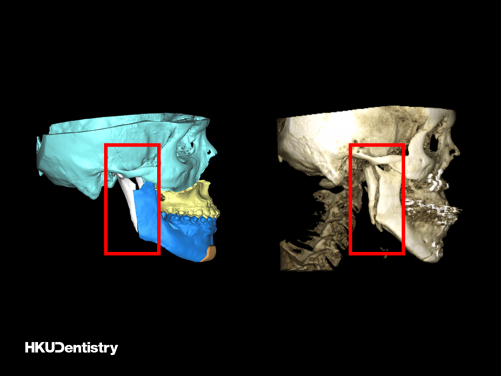

下顎前突症是一種面部畸形,在香港和南中國十分普遍,西方國家相對較少。矯正下顎前突症需要進行正顎手術,手術過程涉及切開顎骨並將它們固定在預先計劃的位置。口內垂直支骨切開術(IVRO)和矢狀支骨切開術(SSRO)是修復過長下顎的兩種常用手術技術。IVRO 是一種較傳統的技術,需要用鐵線固定上下顎 (俗稱鎖口),為期 6 周。在此期間,病人只能進食流質食物。相比之下,SSRO 會使用鈦金屬板和螺絲進行內部固定,手術後即可恢復顎骨功能。這兩項技術在香港和東亞地區都時常採用。